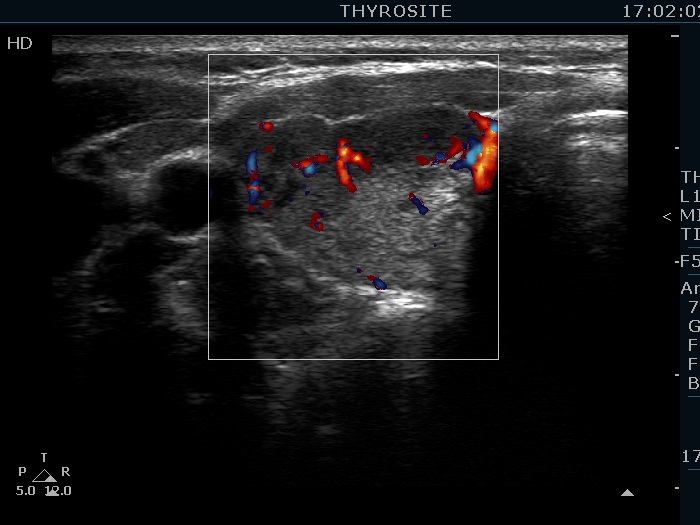

First examination (first row of images):

Clinical data: A 37-year-old woman requested an evaluation of complaints suggesting hypothyroidism. After her second birth two years ago, she was left with an excess weight of 18 kg.

Palpation: no abnormality.

Laboratory tests: TSH 3.52 mIU/L, FT4 14.1 pM/L, aTPO 405 U/mL.

Ultrasonography. The thyroid was echonormal and presented numerous hypoechogenic discrete areas. The echogenicity index was approximately 30%. None of the discrete areas corresponded to pathological nodule. The vascularity was a bit lower than the average.

Suggestion: TSH in a year.